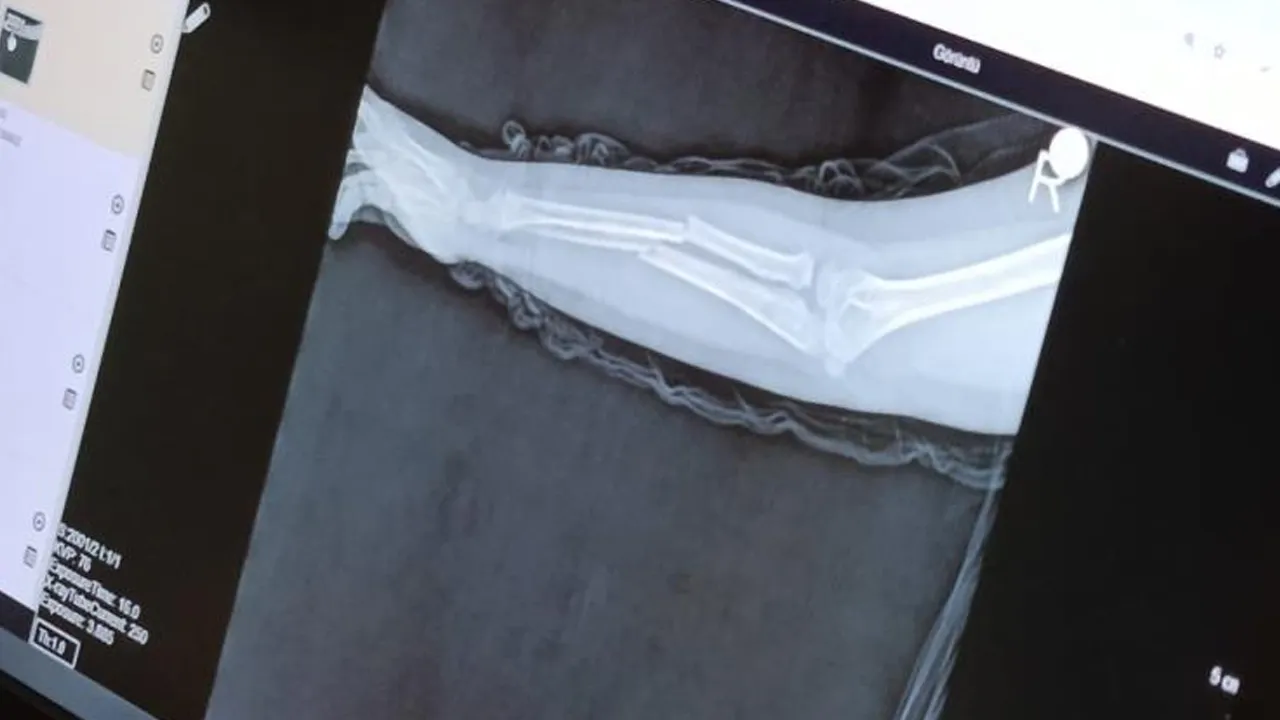

- Y.K.Ş.'nin kolu 2 ayrı yerinden kırıldı.

Geçtiğimiz ay Büyükçekmece Tepecik'te bulunan bir ilkokulda iddiaya göre 8 yaşındaki Y.K.Ş. okulda bir süredir kendisini rahatsız eden 9 yaşındaki çocuk tarafından darbedilerek kolu ikiye katlandı. Y.K.Ş.'nin katlanan kolu 2 ayrı yerinden kırıldı. Öğretmenlerin Y.K.Ş.'nin ailesini arayarak, 'Oğlunuz arkadaşıyla kavga etti duvara çarptı' dediği öne sürüldü.

Oğlunu okuldan alıp hastaneye götüren anne Songül Gökdemir, oğlunun kolunun 2 ayrı yerinden kırıldığını öğrenip ameliyata alınacağını duyduğunda büyük şok yaşadı. Konuyla ilgili anne Gökdemir savcılığa giderek şikayetçi olurken, savcılıktan 'Söz konusu suça sürüklenen çocuğun yaşının 12'den küçük olduğu gerekçesi ile kovuşturmaya yer yoktur' kararı çıktı. Anne Gökdemir karara itiraz ederken mağdur Y.K.Ş. ise haftalardır okuluna gidemiyor. Eğitimi aksayan çocuğun 2 hafta sonra ise platinlerinin çıkarılması için yeniden ameliyata gireceği bildirildi.